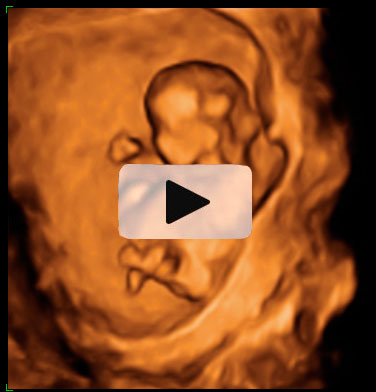

La ecografía permite medir a este feto de 12 semanas. Con esta medición se comprueba cómo crece a lo largo de las semanas. Para ello se toma la distancia que existe entre la coronilla y el final de la columna vertebral.

Embrión con una longitud de 57 milimetros,

Desde la cabeza a la rabadilla, la llamada longitud cráneo-caudal (CRL). Corresponde a 12,1 semanas de gestación.